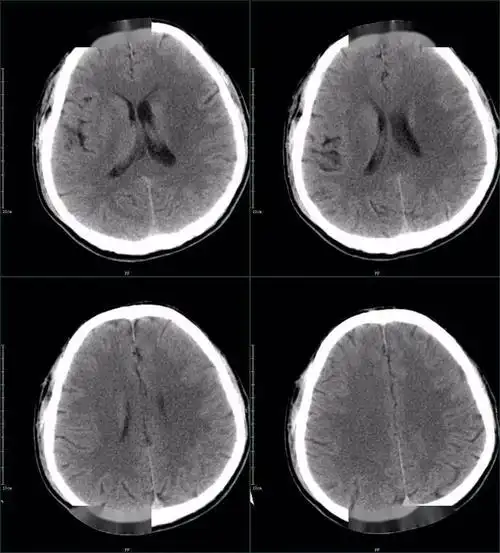

67超急性期大面积脑梗死ct平扫表现

一例脑梗死患者的ct演变及治疗过程